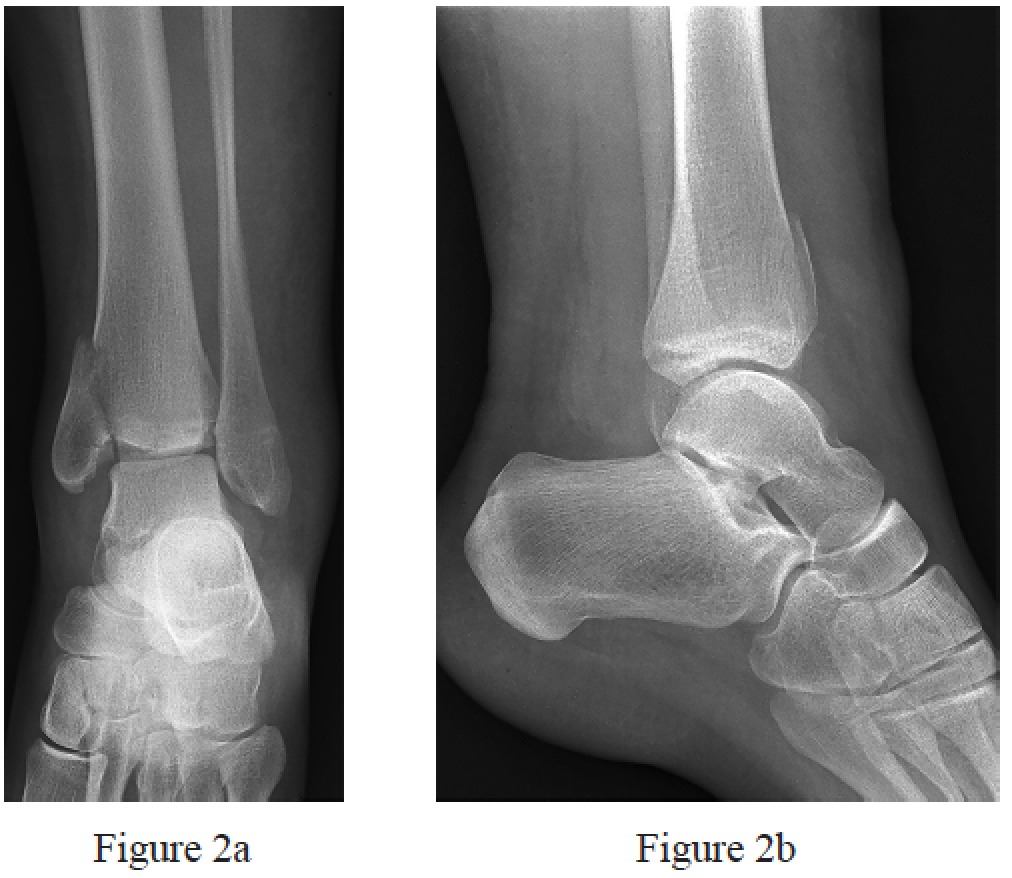

and 2b?

and fixation of the posterior malleolus

tibia and fibular diameter, with no reduction and fixation of the posterior malleolus